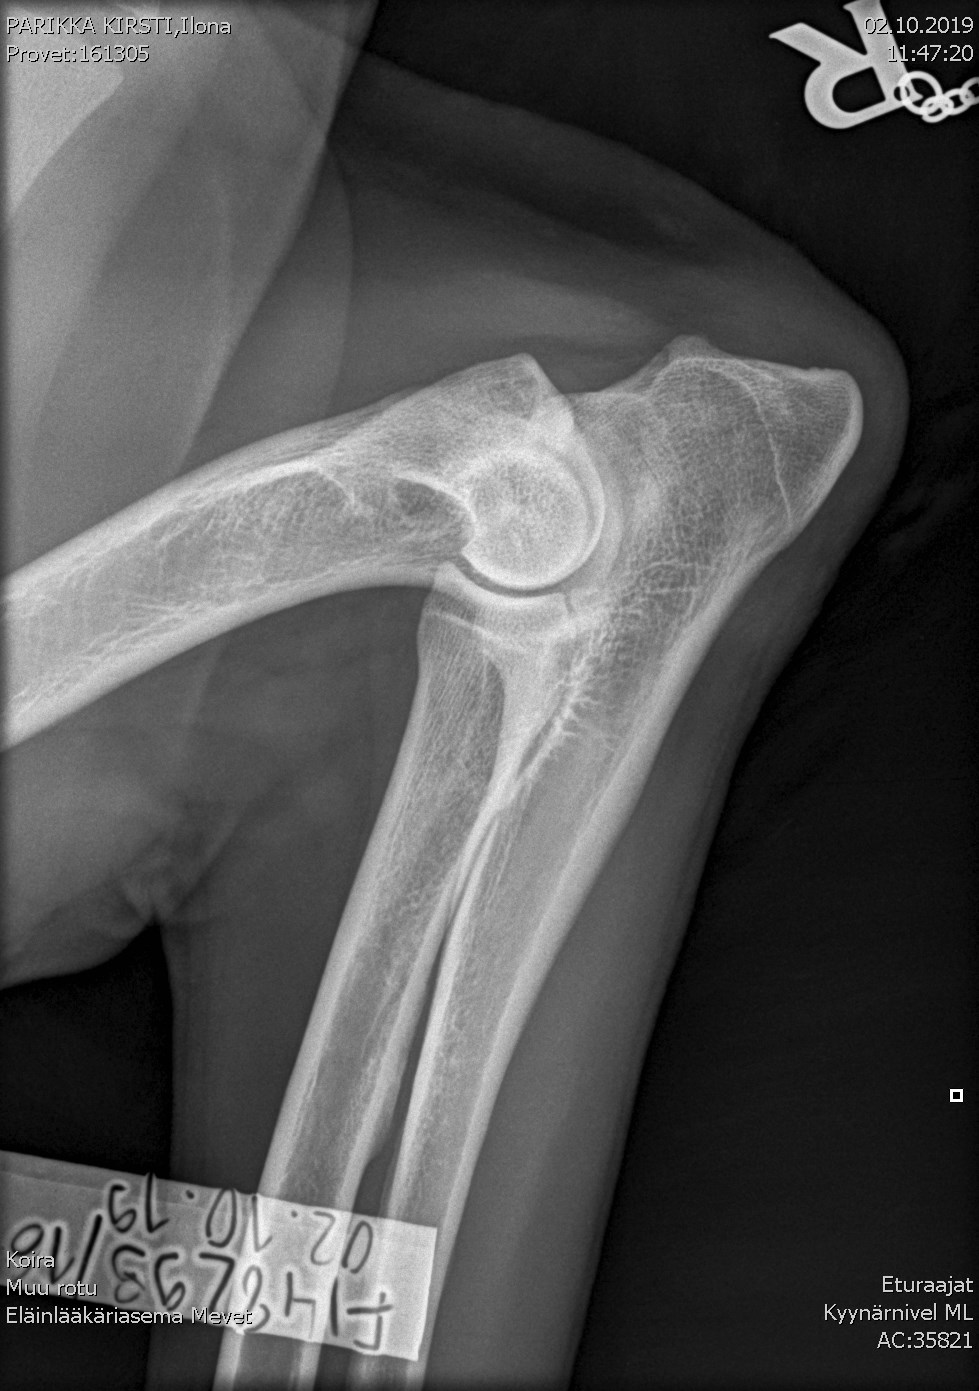

Ilona's elbow X-ray